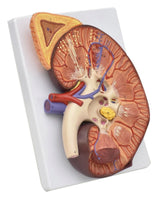

Modelo de Riñón maxizado con Glándula renal rinon

Modelo de Riñón maxizado con Glándula renal riñón

sistema urinario maximizado

Medidas del producto: 21 x 28 x 9 cm